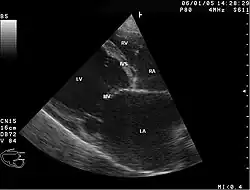

Abnormal heart sounds, murmurs, ECG abnormalities, and enlarged heart on chest x-ray may lead to the diagnosis. Echocardiogram abnormalities and cardiac catheterization or angiogram to rule out coronary artery blockages, along with a history of alcohol abuse can confirm the diagnosis.[4] It's important to note that part of diagnosing Chronic ACM is noting the absence of coronary artery disease.[7] It's also worth noting that the diagnosis of ACM is largely a diagnosis of exclusion.

In addition to the patient's medical history and physical exam, the diagnosis of alcoholic cardiomyopathy is often confirmed with various diagnostic tests.[8] One of the most common tests is an echocardiogram, which uses ultrasound waves to create images of the heart and can detect abnormalities in the heart's structure and function.[8] Other tests may include an electrocardiogram (ECG) to measure the heart's electrical activity, and blood tests to check for elevated levels of certain enzymes that may indicate heart damage.[8] If the diagnosis is confirmed, treatment typically involves stopping alcohol consumption and managing heart failure symptoms through medications, lifestyle changes, and in severe cases, heart transplantation.[8]